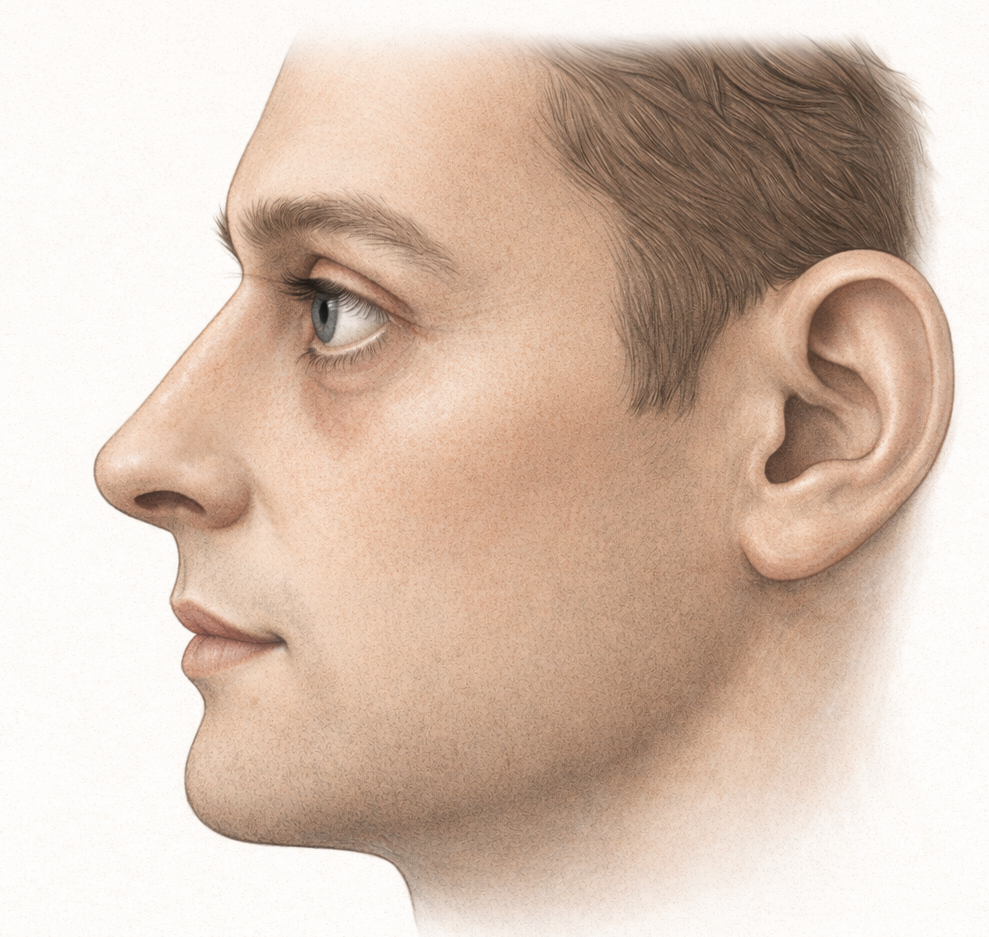

- Tear trough hollowing

- Lower eyelid retraction or increased scleral show

- Higher risk of lower eyelid malposition after blepharoplasty

- A fatigued or skeletonized facial appearance